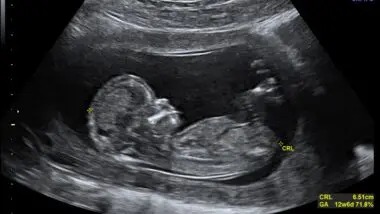

• CRL Crown rump length 12 weeks ecografia Dr. Wolfgang Moroder